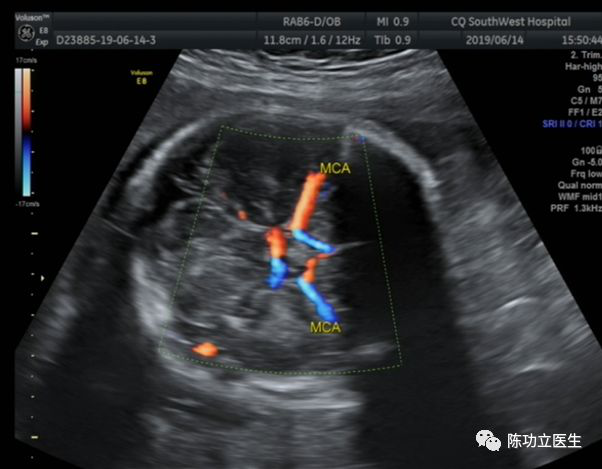

产前诊断标准:不存在羊水过少-羊水过多序列,供血儿胎盘增厚;供血儿大脑中动脉收缩期峰值流速(MCA-PSV)>1.5MOM,受血儿MCA-PSV<1.0MOM。超声医生,辛苦啦(双胎超声很麻烦,谁做谁知道)!

上图来源于重庆西南医院超声科薛雅方医生

1期:供血儿MCA-PSV>1.5MOM,受血儿MCA-PSV<1.0MOM,无其他受损征象;

2期:供血儿MCA-PSV>1.7MOM,受血儿MCA-PSV<0.8MOM,无其他受损征象;